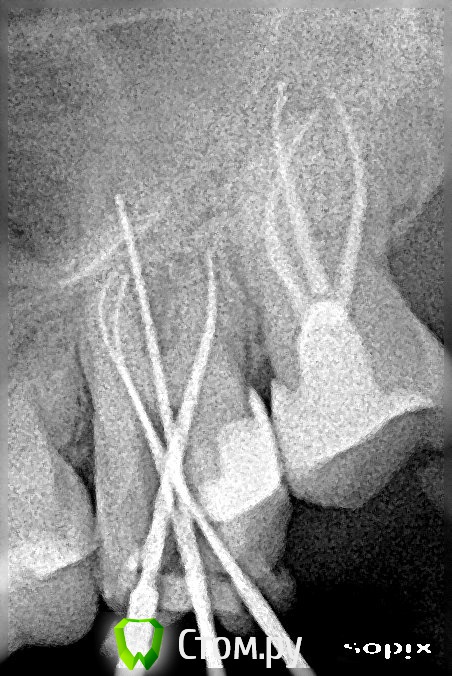

Miria Опубликовано 26 мая, 2014 Поделиться Опубликовано 26 мая, 2014 Здравствуйте!В начале марта 2014 г. лечила 28 (периодонтит острый серозный, зуб болел с декабря 2013 г.) под анестезией, лекарство и временная пломба на 1-м приеме, пломбировка 3-х каналов термафил и постоянная пломба на 2-м приеме (через 8 дней). После лечения болей не было.1 апреля лечила 27 (пульпит хронический в стадии обострения фиброзный, зуб болел с декабря 2013 г.) под анестезией, пломбировка 4-х каналов термафил на 1-м приеме, постоянная пломба на 2-м приеме (через 9 дней). После лечения зуб болел 4 дня, сразу появилось: тепло в области левых скулы и виска; распирание всего зуба, которое усилилось далее; подергивание нерва глубоко в левой щеке ближе к носу. Через 10 дней началось онемение в области левых скулы и глаза, позднее резко ухудшалось зрение. Зуб был болезненный при задевании, ломота, неприятный вкус слюны около 27.25 апреля был распломбирован один канал (небный) и пройден до верхушки, оставлено лекарство, временная пломба (по плану на 24 дня). Прошло онемение скулы и глаза, восстановилось зрение. Распирание, ломота, болезненность, тепло в виске и скуле, подергивание нерва в щеке продолжались и случился сильный приступ боли через 7 дней.3 мая снята временная пломба, лекарство, временная пломба. Пропила назначенный Рулид 5 дней по 1 таблетке 2 раза в день. Исчез неприятный вкус слюны. Распирание, ломота, болезненность, тепло в виске и скуле, подергивание нерва в щеке продолжались.7 мая снята временная пломба, частично распломбирован еще один канал (который по снимку ближе к 26), лекарство, временная пломба. Подергивание нерва в щеке и тепло немного уменьшились. Распирание, ломота, болезненность продолжались.19 мая (24-й день после распломбировки небного канала) снята временная пломба, немного распломбирован еще один канал (который по снимку ближе к 28), запломбирован небный канал, временная пломба.Распирание, ломота, болезненность при задевании, покалывание в щеке, постоянное подергивание нерва в щеке (ближе к носу) продолжаются. Не совсем прошла боль в виске. На снимке выведена пломбировка за апекс.Очень переживаю за зуб. Вопросов много и срочные, может, что еще скажете.1. Почему может болеть зуб 27?2. Какова методика дальнейшего лечения 27?3. Нужно ли убирать выведенный материал, если он дает такую реакцию? Или со временем боль может пройти (такая боль продолжается с первого приема лечения с 01.04.2014, терпению давно предел)?4. Может ли получиться убрать выведенный материал за верхушками через распломбированные каналы или как? (По-моему хирургически просто не добраться) И если вновь распломбировывать – то распломбировывать надо сразу все каналы (небный канал запломбирован два раза)?5. Повторное эндодонтическое лечение намного хуже для зуба или как оно влияет на дальнейшее функционирование зуба?Спасибо огромное за Ваши время и ответ, который очень жду! 1 Ссылка на комментарий

Miria Опубликовано 12 июня, 2014 Автор Поделиться Опубликовано 12 июня, 2014 Здравствуйте, добавляю снимки. Ссылка на комментарий